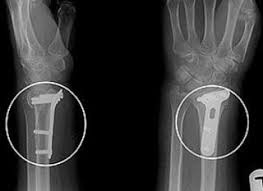

Patienten älter als 55 Jahre mit vorbestehender Bewegungseinschränkung und dislozierter distaler Radiusfraktur und unzureichender Konsolidierung 6 Wochen posttraumatisch wurden als Risikopatienten für ein schlechteres Outcome identifiziert hier wurde die Empfehlung zur Durchführung von Physiotherapie gestellt. Postoperative Röntgenkontrolle einer distalen Radiusfraktur nach Osteosynthese mit zwei winkelstabilen Platten Weiterbehandlung keine Ruhigstellung des gesamten Arms sondern frühzeitige Bewegungsübungen angrenzender Gelenke Finger Ellenbogen Schulter im. In guter Stellung verheilte Radiusfraktur Achsenabkippung geringeren Grades mit einer Bewegungseinschränkung von insgesamt 40.

Mitunter treten begleitend zum Speichenbruch Sensibilitätsstörungen der Hand oder der Finger auf. Patienten älter als 55 Jahre mit vorbestehender Bewegungseinschränkung und dislozierter distaler Radiusfraktur und unzureichender Konsolidierung 6 Wochen posttraumatisch wurden als Risikopatienten für ein schlechteres Outcome identifiziert hier wurde die Empfehlung zur Durchführung von Physiotherapie gestellt. Je nach Ausmaß der Verletzung kommt es zu einer Dislokation also einer Verschiebung des Frakturfragments. Nun hab ich eine Metallplatte noch drin. Im Langzeitverlauf ist in Abhängigkeit von der Frakturstellung - die Entstehung einer posttraumatischen Arthrose Gelenkverschleiß möglich. Gesichert werden kann die Radiusfraktur aber meist nur mithilfe einer Röntgendiagnostik. Nach mehreren Therapien ist mein Handgelenk zwar beweglicher geworden aber nach hinten kann ich es gar nicht beugen.